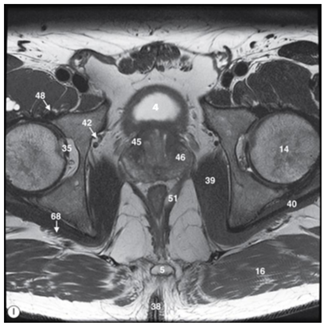

Observa a imagem a seguir.

Na RM acima, ponderada em T2, os números 4, 45 e 46 equivalem às seguintes estruturas: